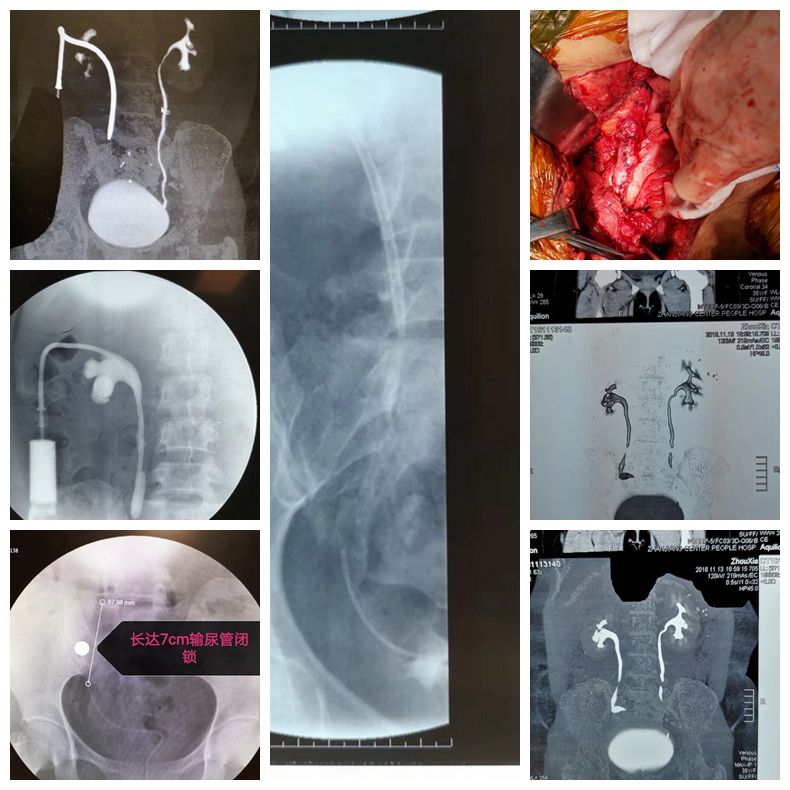

开放性膀胱瓣输尿管成型术治疗妇科手术术后造成的输尿管中下段长距离闭锁的病例

科室积致力于泌尿外科微创技术的创新和优化。在广泛开展腹腔镜肾癌根治术、肾部分切除术、前列腺癌根治术、全膀胱切除术及肾上腺肿瘤切除术等基础上,进一步扩大腹腔镜技术的覆盖范围,开展腹腔镜下腹膜后和盆腔扩大淋巴结清扫术等高难度手术。推动外科微创化与加速康复外科(ERAS)的紧密结合,打造成特色、优势技术,受到广大患者认可。泌尿系统结石疾病的诊治是我科的传统优势项目,保持着省内先进水平。我科应用经皮肾镜技术开展了一些高难度的肾结石手术,如严重脊柱畸形患者的肾结石、孤立肾肾结石、无肾积水的肾结石、马蹄肾肾结石等,而且手术均取得成功。泌尿系肿瘤的发病率逐年升高,其防治任重而道远。我科积极开展复杂性泌尿系肿瘤的诊治,尤其是巨大肾上腺肿瘤、巨大肾肿瘤、孤立肾较大肾癌的保留肾脏手术等。同时积极开展泌尿系肿瘤的防治研究,重点进行泌尿系肿瘤病因学的研究,尤其是寻找膀胱癌、肾癌和前列腺癌相关功能基因,从基因学角度寻找肿瘤特异标记物,提高泌尿系肿瘤早期诊断水平,并为进一步基因治疗提供基础。前列腺增生作为老年男性常见疾病一直以来是我们重点研究的方向和医疗特色之一。随着外科技术的不断进步及新的医疗设备的不断涌现和完善,TURP的金标准地位逐渐受到挑战,如经尿道钬激光前列腺剜除术技术日臻完善,大有取代TURP之势。目前我科已积极开展经尿道钬激光在良性前列腺增生治疗中的应用,取得了良好的治疗效果。我科针对目前男性疾病诊治需求量迅速增加的现状,积极开展男科的特色诊疗,范围包括男子勃起功能障碍、早泄、男性不育症、精索静脉曲张、血精、阴茎硬结症、睾丸附睾疾病、男子生殖系统内分泌疾病等。开科以来典型手术介绍如下: